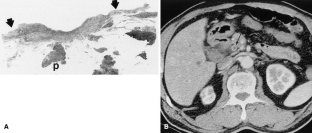

Fig. 1.